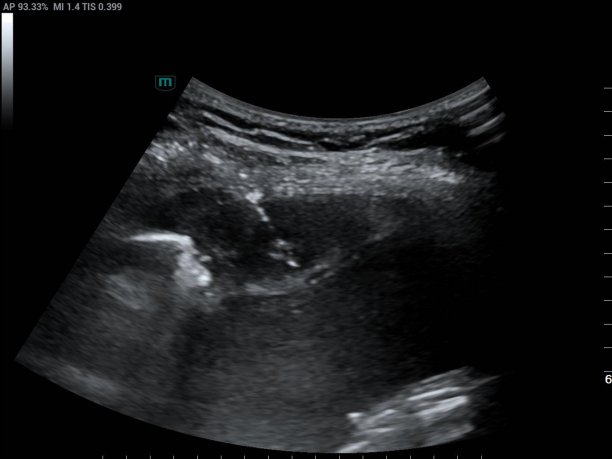

超声医学科主任潘国栋与主治医师刘金昊依据超声显示的病变范围,细致规划了穿刺点、进针路线及深度,避开了肋间动脉、神经及病变侧方的肺组织。全程在超声的实时引导下,穿刺针精准到达病变部位,采集了2条病变组织。

经超声引导下避开血管、实时显示穿刺针从进入胸膜结节到击发穿刺针的全过程